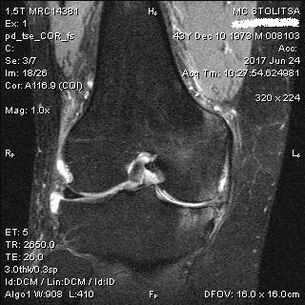

The diagnosis of arthrosis of the knee joint is made in the office of a rheumatologist or orthopedist.The doctor examines the affected joint, palpates it, listens to complaints and asks additional questions.Performs several tests - for example, asking the patient to bend the leg or walk a few steps.Then, if it is necessary to clarify the stage of the disease or the nature of pathological changes, he will refer you for additional studies.For example, for computed tomography or radiography.